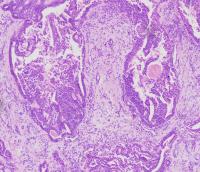

鼻翼粘液表皮样癌??

性别

男

年龄

60岁

鼻翼肿块

标本名称

大体所见

1*1cm灰白色肿块

考虑粘液表皮样癌,请各位老师会诊。谢谢。

考虑皮肤混合瘤

考虑多形性腺瘤

倾向混合瘤。

经会诊为:多形性腺瘤。